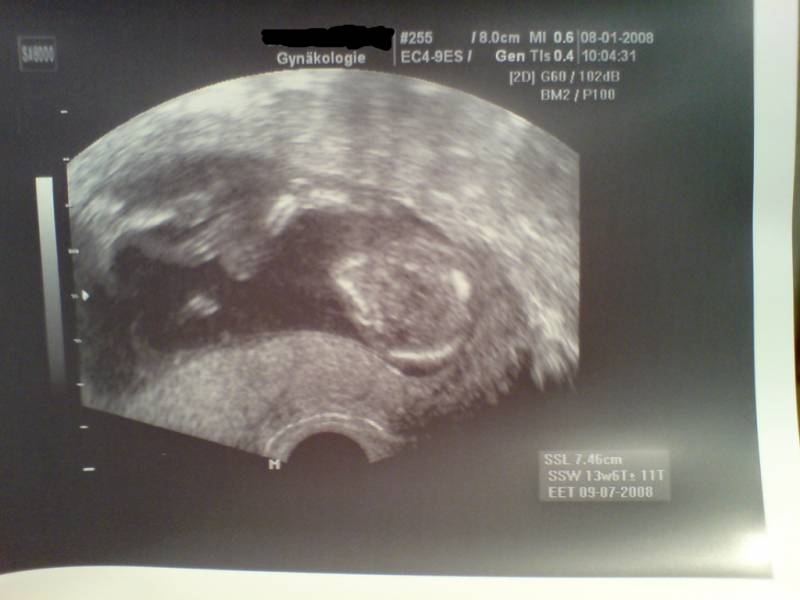

14_1 15. SSW Datum 19.05.2008 15. SSW

14_2 15. SSW Datum 19.05.2008 15. SSW